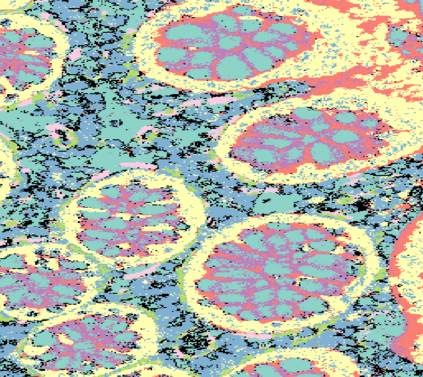

The usage of chemical imaging technologies is becoming a routine accompaniment to traditional methods in pathology. Significant technological advances have developed these next generation techniques to provide rich, spatially resolved, multidimensional chemical images. The rise of digital pathology has significantly enhanced the synergy of these imaging modalities with optical microscopy and immunohistochemistry, enhancing our understanding of the biological mechanisms and progression of diseases. Techniques such as imaging mass cytometry provide labelled multidimensional (multiplex) images of specific components used in conjunction with digital pathology techniques. These powerful techniques generate a wealth of high dimensional data that create significant challenges in data analysis. Unsupervised methods such as clustering are an attractive way to analyse these data, however, they require the selection of parameters such as the number of clusters. Here we propose a methodology to estimate the number of clusters in an automatic data-driven manner using a deep sparse autoencoder to embed the data into a lower dimensional space. We compute the density of regions in the embedded space, the majority of which are empty, enabling the high density regions to be detected as outliers and provide an estimate for the number of clusters. This framework provides a fully unsupervised and data-driven method to analyse multidimensional data. In this work we demonstrate our method using 45 multiplex imaging mass cytometry datasets. Moreover, our model is trained using only one of the datasets and the learned embedding is applied to the remaining 44 images providing an efficient process for data analysis. Finally, we demonstrate the high computational efficiency of our method which is two orders of magnitude faster than estimating via computing the sum squared distances as a function of cluster number.